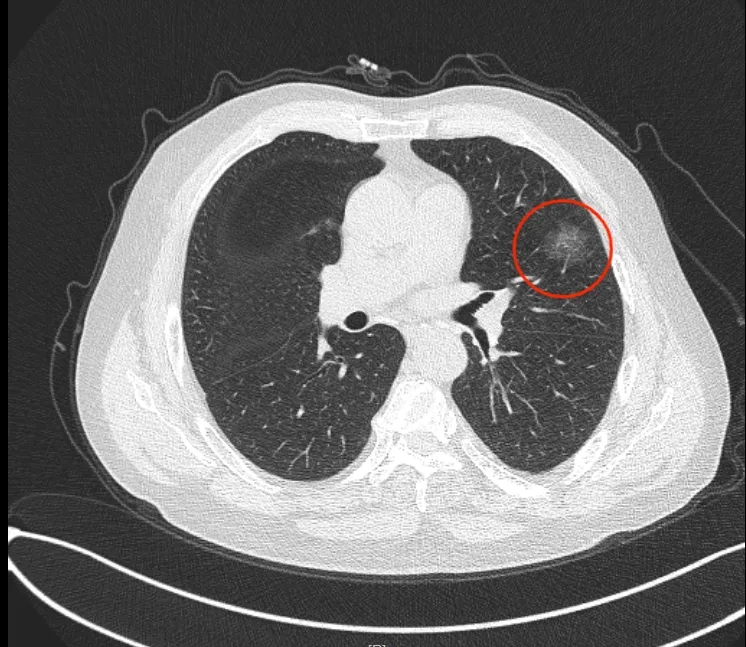

檢查發(fā)現(xiàn)

左肺上葉

一個直徑約25mm

磨玻璃結(jié)節(jié)

影像科醫(yī)生懷疑

這可能是早期肺癌表現(xiàn)

這次入院

醫(yī)學(xué)影像科副主任許韶遠(yuǎn)會診后

發(fā)現(xiàn)李大爺?shù)哪ゲAЫY(jié)節(jié)

范圍比以前有所擴(kuò)大

密度增加

這進(jìn)一步證實(shí)了

對早期肺癌的診斷